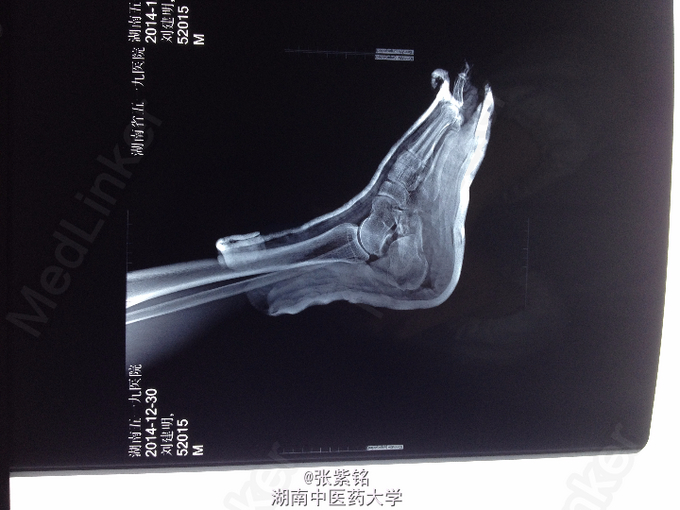

查体:左足部肿胀明显,可见大面积皮下青紫瘀斑,压痛明显,尤以足跟部为甚,左足跟部可扪及明显骨擦音,足踝关节主动活动受限,被动活动疼痛明显加重,左足背动脉搏动可扪及,伤肢血运感觉可。 辅查:左足正斜位片示:左跟骨骨折。 左足CT平扫+三维重建:左跟骨骨质连续性中断,可见多发骨折线,骨折端对位对线不良,并可见多块碎骨片,骨折线累积关节面,左足软组织明显肿胀;左跟骨粉碎性骨折。